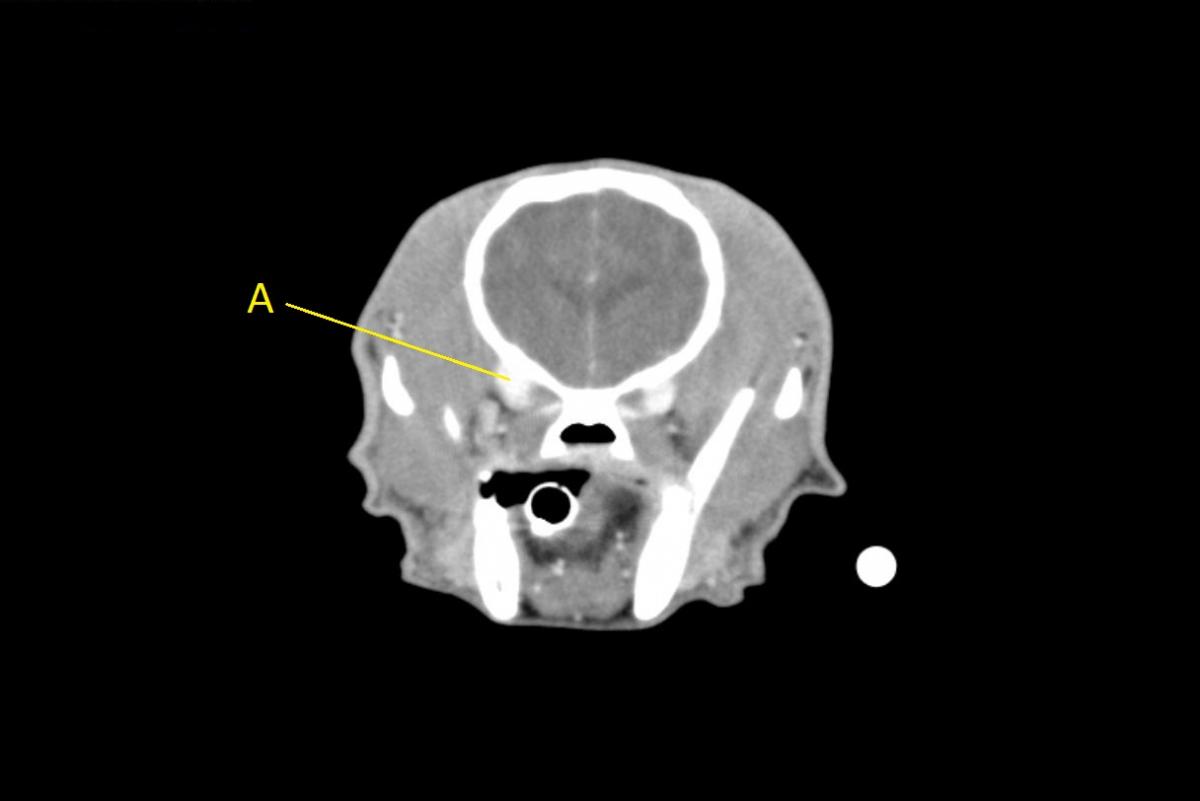

Q. Identify the structures labeled below:

A. ophthalmic venous plexus